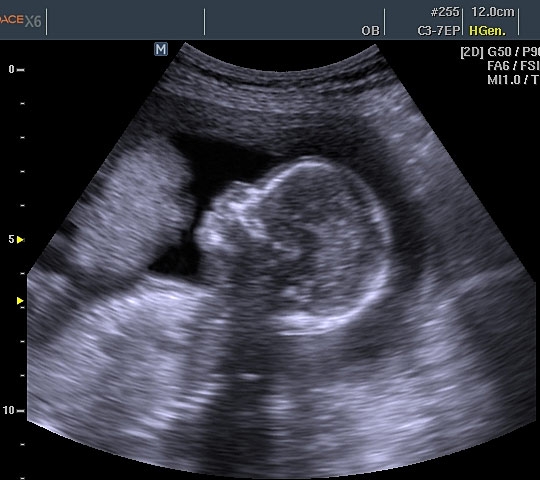

УЗИ: 12-ая неделя беременности

Пришло время для одного из самых значимых ультразвуковых исследований. На двенадцатой неделе беременности УЗИ становится обязательным этапом диагностики. В ходе обследования помимо измерения размеров плода, проводятся замеры головы, плечевых, локтевых, бедренных, лучевых, большеберцовых и малоберцовых костей. Также оценивается симметрия конечностей и их двигательная активность, а также правильное расположение сердца и желудка. На этом сроке с высокой вероятностью можно выявить возможные пороки сердца. Важно измерить толщину воротниковой зоны, которая в норме не должна превышать 2.5 миллиметров; превышение этого значения может указывать на риск хромосомных аномалий, таких как синдром Дауна. Врач также внимательно изучает носовые кости плода, так как у детей с синдромом Дауна они, как правило, короче. Это связано с тем, что формирование носовых костей при данной патологии завершается значительно позже, чем у здоровых плодов. Таким образом, визуализация носовых костей на УЗИ на двенадцатой неделе является важным диагностическим показателем.